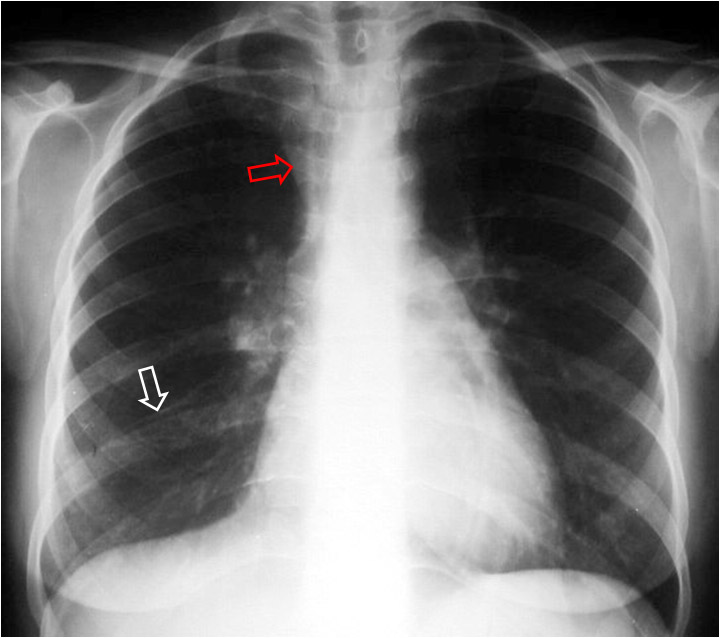

SIGNO DEL TRIÁNGULO SUPERIOR

Signo de colapso del lóbulo medio derecho o del lóbulo inferior derecho que consiste en la presencia de una densidad triangular en la zona paramediastínica derecha (flecha roja) que corresponde a la zona de convergencia de las líneas pleuromediastínicas anteriores, desplazadas a la derecha por el colapso. El descenso de la posición de la cisura menor (flecha blanca) confirma la pérdida de volumen en el lóbulo medio, en este caso.